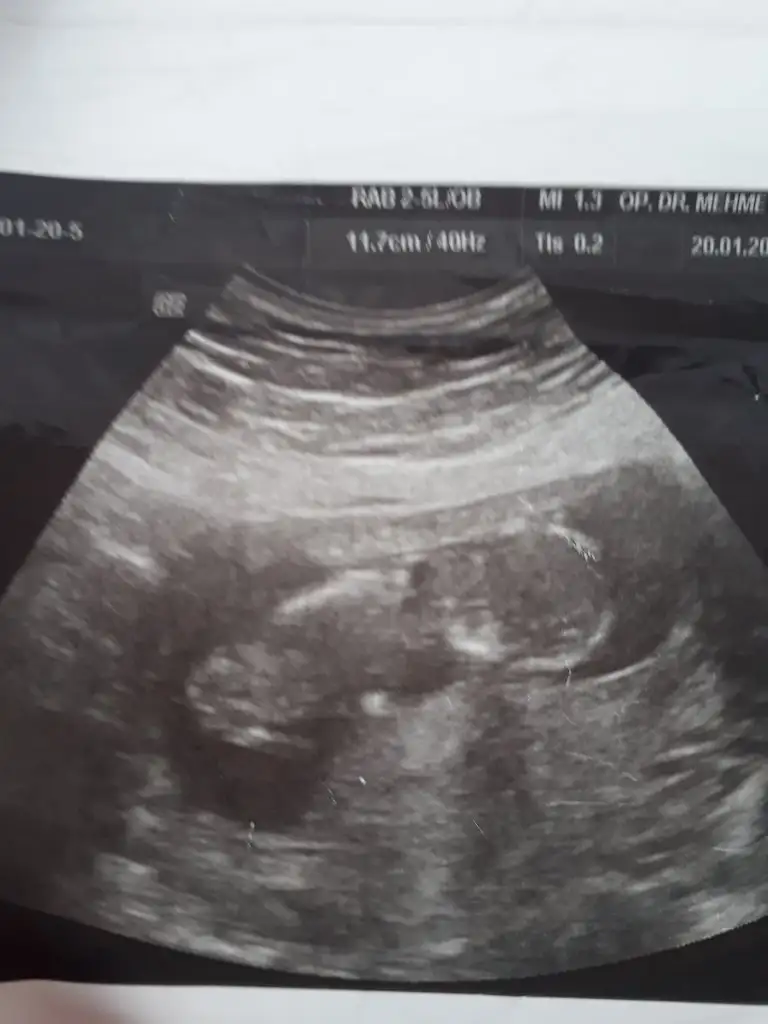

Bide bunlara bak bakalım cnm12hafta 6günlükEki Görüntüle 2585761

11 yada 129 haftalığız Acaba bizede tahmin yapabilirmisiniz yoksa 11 12yimi beklemeliyim![]()

Kaç haftalık sanki kız gibi 12 hafta paylaşınBanada bi tahminiz var mı![]()

13 haftalık :) doktor söylemedi cinsiyetini yanıltıcı olabilir dedi. Tahmini ni bile söylemediKaç haftalık sanki kız gibi 12 hafta paylaşın

Başka usg varmı teyit edim13 haftalık :) doktor söylemedi cinsiyetini yanıltıcı olabilir dedi. Tahmini ni bile söylemedi. Teşekkür ederim